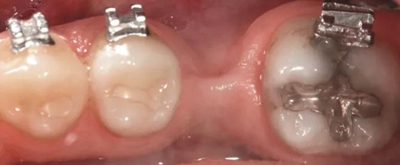

圖5a. 病例2中右下第一磨牙加速種植位點改建。初期排齊期間

圖5b. 術(shù)前臨床檢查

圖5c. 翻全厚瓣后,看到嚴重的牙槽嵴吸收

圖5d. 在骨移植受植處、第二磨牙和第三磨牙牙根之間以及第三磨牙遠中進行去皮質(zhì)術(shù)

圖5e. 去皮質(zhì)后,同種異體凍干骨顆粒放置于受植區(qū)

圖5f. 膠原膜覆蓋并適應于受植區(qū)

圖5g. 3 個月后完成了位點加速改建,近遠中向的修復空間和頰舌向的骨增量均增加

圖5h. 通過帶有一個后傾彎的鋼絲以及開放彈簧的半托槽距離輕加力實現(xiàn)了生物力學直立磨牙